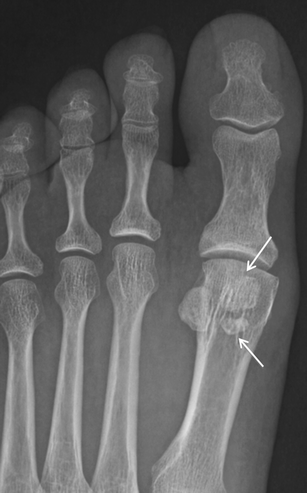

Hallucal sesamoid fracture. Oblique (a) and AP (b) radiographs at the forefoot in a patient after deceleration injury. There are dorsal dislocations of the first and second metatarsophalangeal joints (black arrows), with a comminuted fracture of the lateral hallucal sesamoid (white arrows). Note that the sesamoid fracture pieces would fit together perfectly. The medial hallucal sesamoid is also fractured in this patient

Osteomyelitis. a AP radiograph in a patient with a plantar ulcer showing cortical dehiscence and destructive change at the medial sesamoid (black arrow) suggestive of osteomyelitis. Note severe adjacent soft tissue swelling (white arrow). b AP radiograph in the same patient approximately 5 weeks later with near complete destruction of the medial hallucal sesamoid (black arrow) and persistent soft tissue swelling (white arrow). The great toe was amputated